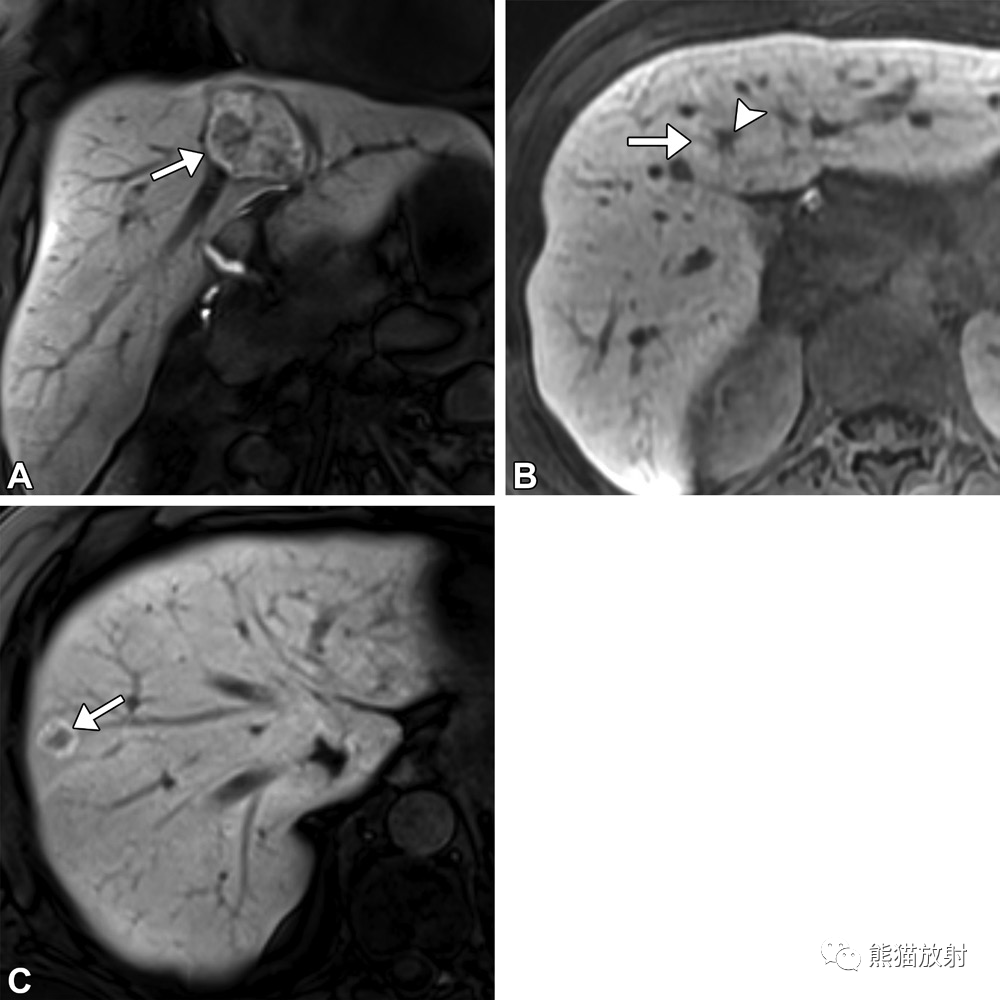

24岁女性,Budd-Chiari综合征(BCS),散在多发FNH样病变。T1WI预扫(A),T2WI(B)和增强肝胆期(C)MR图像显示,与FNH不同,BCS中的FNH样病变常表现为T1高信号和T2低信号,但在其他方面表现为典型特征,包括肝胆期对比剂高摄取。